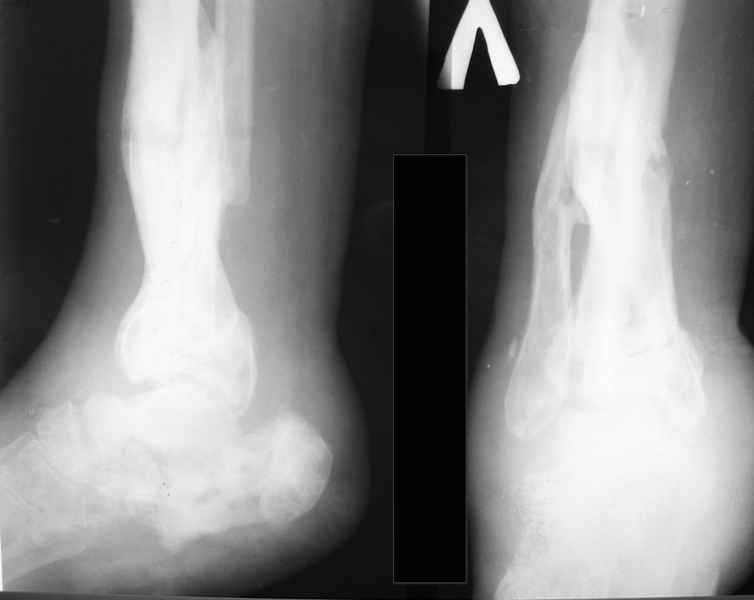

Молодая девушка со сросшимися многооскольчатыми переломами пяток и голеней.Young girl with fractures of the calcaneus Больная Н., 25 лет, падение с высоты (2008 г.). Жалобы на боли в области голеностопных суставах, в области пяток при ходьбе. Лечилась в аппаратах внешней фиксации по поводу открытых оскольчатых переломов обеих голеней, переломов пяток. Далее по поводу несросшихся переломов голеней –ЧКОС аппаратами внешней фиксации. Переломы срослись, аппараты демонтированы весной 2010г. В левой пяточной области в месте проведения спицы имеется сукровичное отделяемое. При ревизии гноя нет. Чем помочь девушке?

Patient N., age 25, falls from heights (2008). Complaints of pain in the ankles, in the heel when walking. She was treated by external fixation on open comminuted fractures of both legs, fractures of the calcaneus. Then she was treated by external fixation from nonunion of both legs. Now fractures are fused, apparatuses removed in the spring of 2010. How to help a girl?

я бы начал с осевых снимков голени (как минимум. лучше всей конечности) и фото ноги, несмотря на жутковатую картину пятки, подобные пациенты часто неплохо компенсированы (сам такой), возможно беспокоят не столько пятка. сколько деформация голени